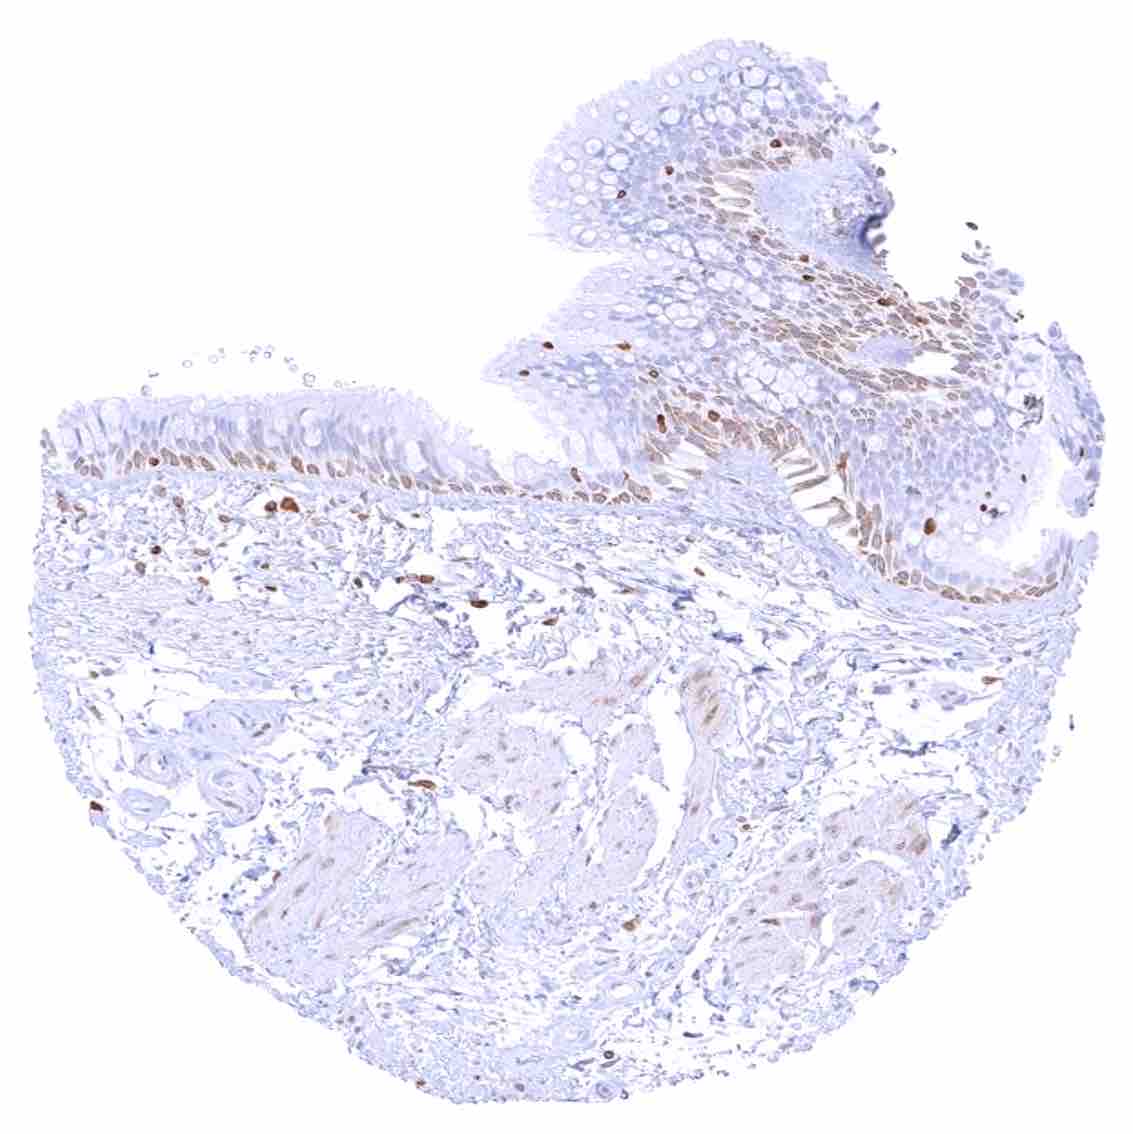

Duodenum, mucosa – Cytoplasmic bcl-2 staining is largely limited to lymphocytes. The epithelium is mostly negative, but a weak staining occurs in some crypt cells.